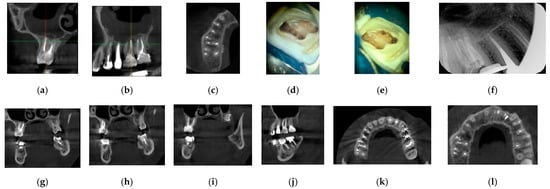

2.1. Clinical Case 1

2.2. Clinical Case 2

2.3. Clinical Case 3